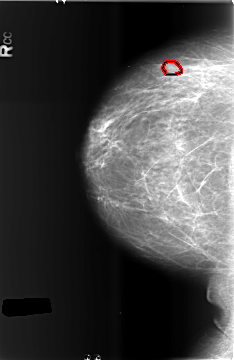

B_3432_1.RIGHT_CC

RIGHT_CC LINES 5752 PIXELS_PER_LINE 3736 BITS_PER_PIXEL 12 RESOLUTION 50 OVERLAY

FILE: B_3432_1.RIGHT_CC.OVERLAY

TOTAL_ABNORMALITIES 1

ABNORMALITY 1

LESION_TYPE MASS SHAPE OVAL MARGINS CIRCUMSCRIBED-OBSCURED

ASSESSMENT 4

SUBTLETY 3

PATHOLOGY BENIGN

TOTAL_OUTLINES 1

BOUNDARY